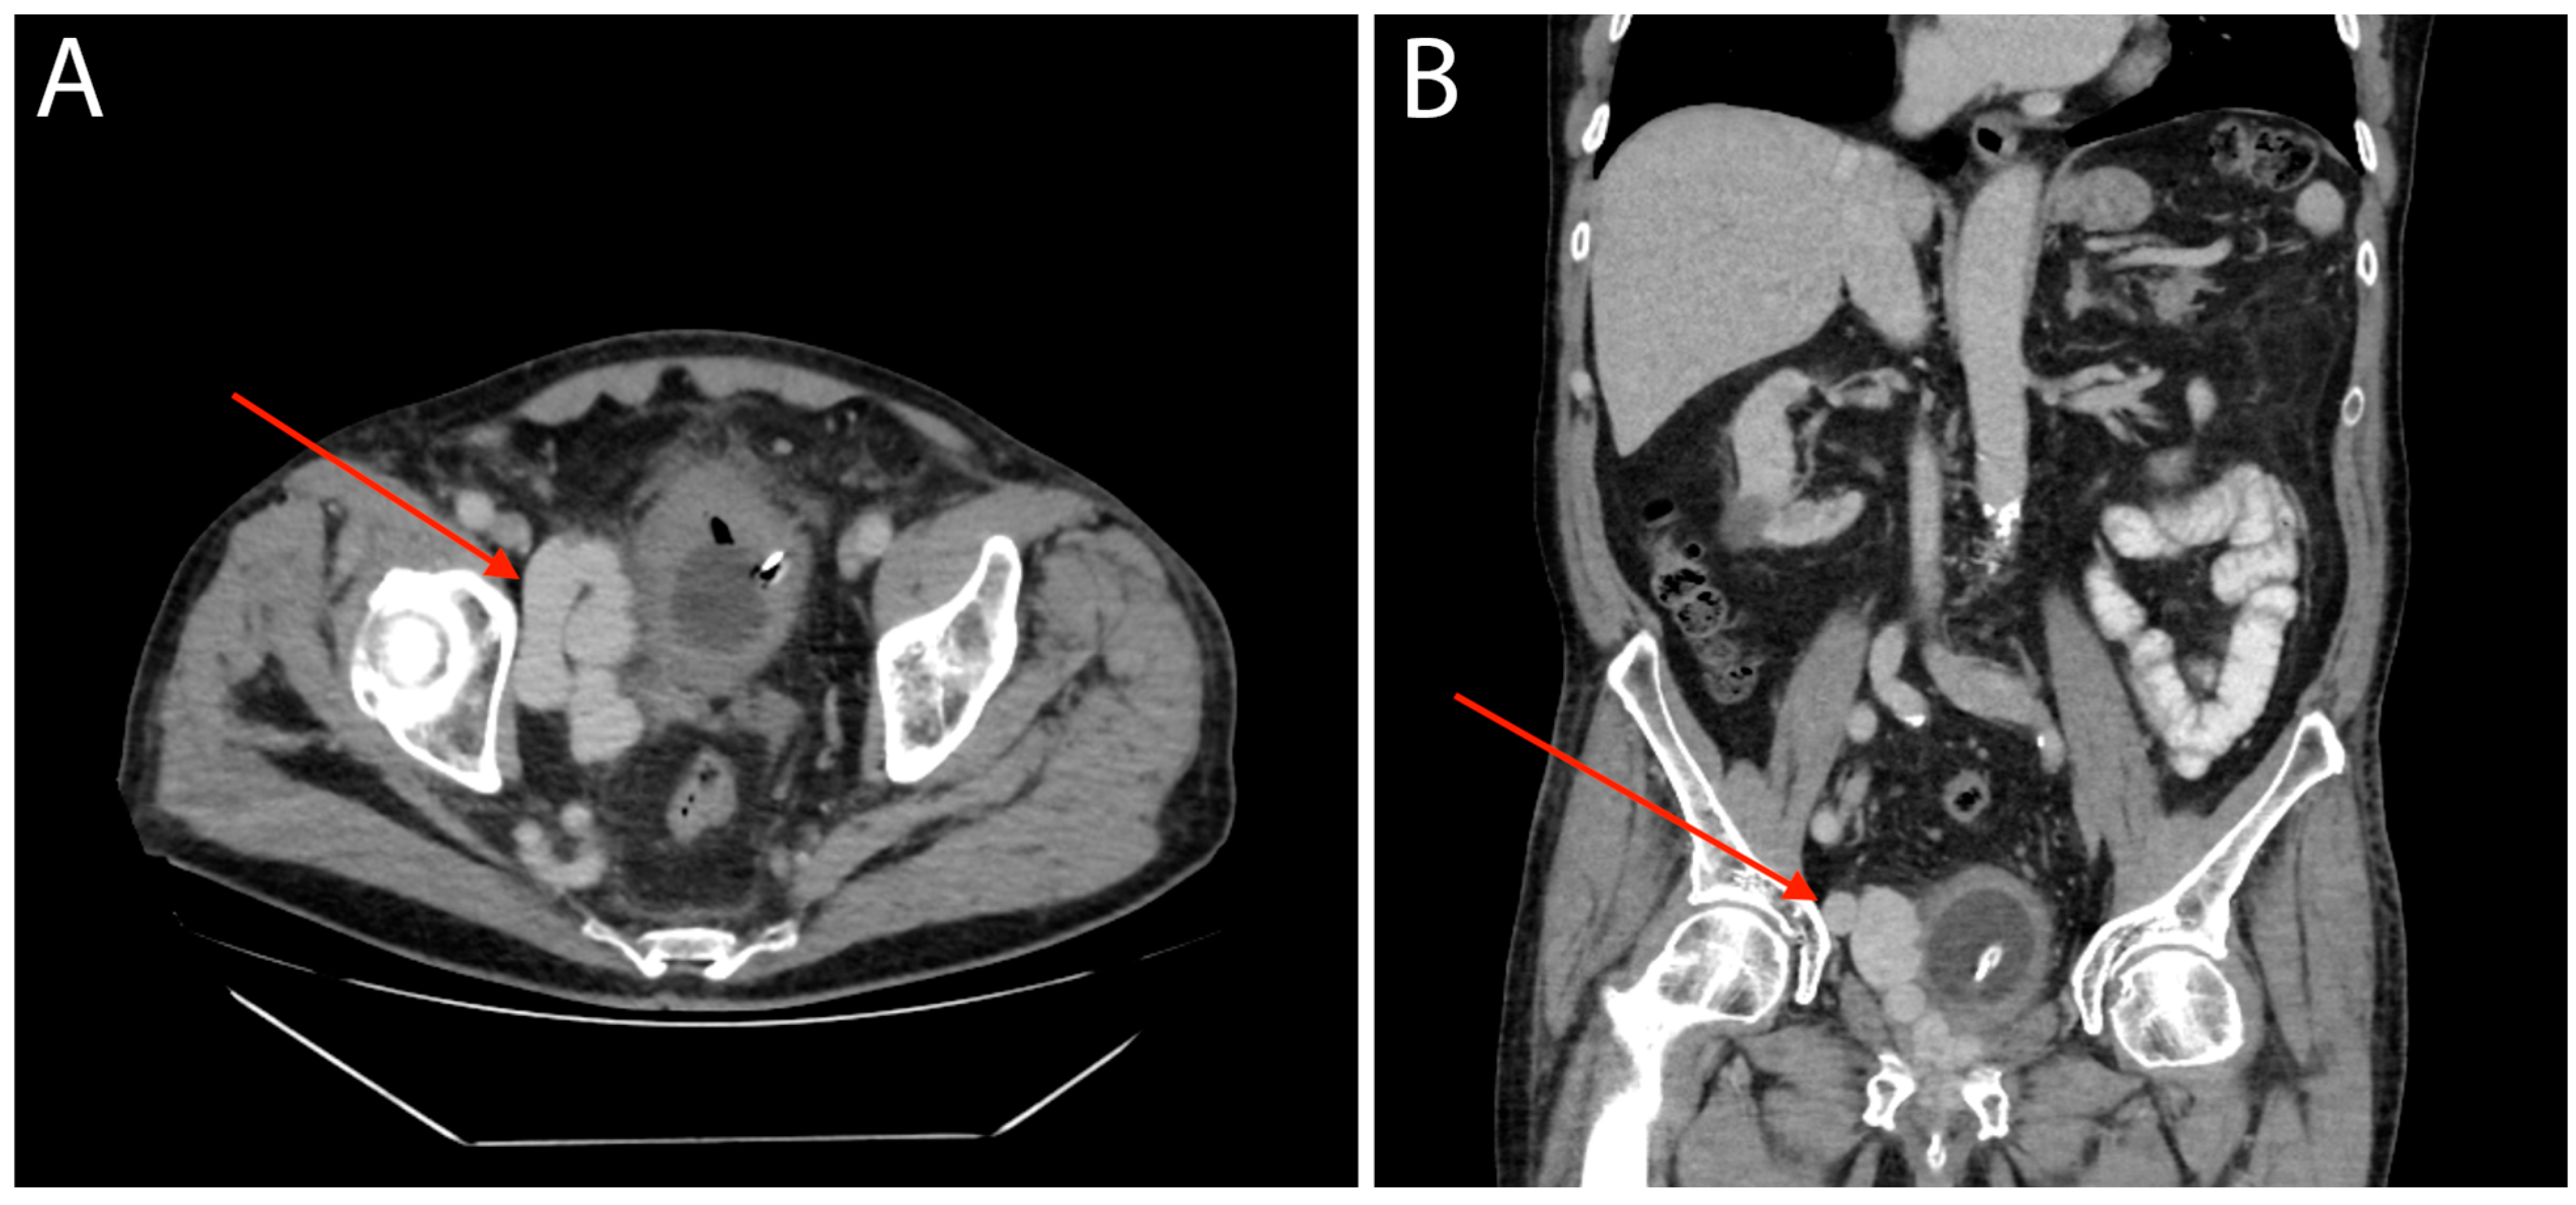

Arteriovenous Malformation of the Prostate Vasculature as a Cause of Torrential Bleeding during Transurethral Resection of the Prostate